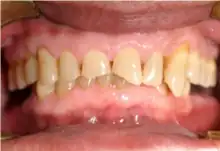

Mouth

Acid reflux into the mouth can cause breakdown of the enamel, especially on the inside surface of the teeth. A dry mouth, acid or burning sensation in the mouth, bad breath and redness of the palate may occur.[21] Other not so common symptoms of GERD include difficulty in swallowing, water brash which is flooding of the mouth with saliva, chronic cough, hoarse voice, nausea and vomiting.[20]

Signs of enamel erosion are the appearance of a smooth, silky-glazed, sometimes dull, enamel surfaces with the absence of perikymata, together with intact enamel along the gum margin.[22] It will be evident in people with restorations as tooth structure typically dissolves much faster than the restorative material, causing it to seem as if it “stands above” the surrounding tooth structure.[23]